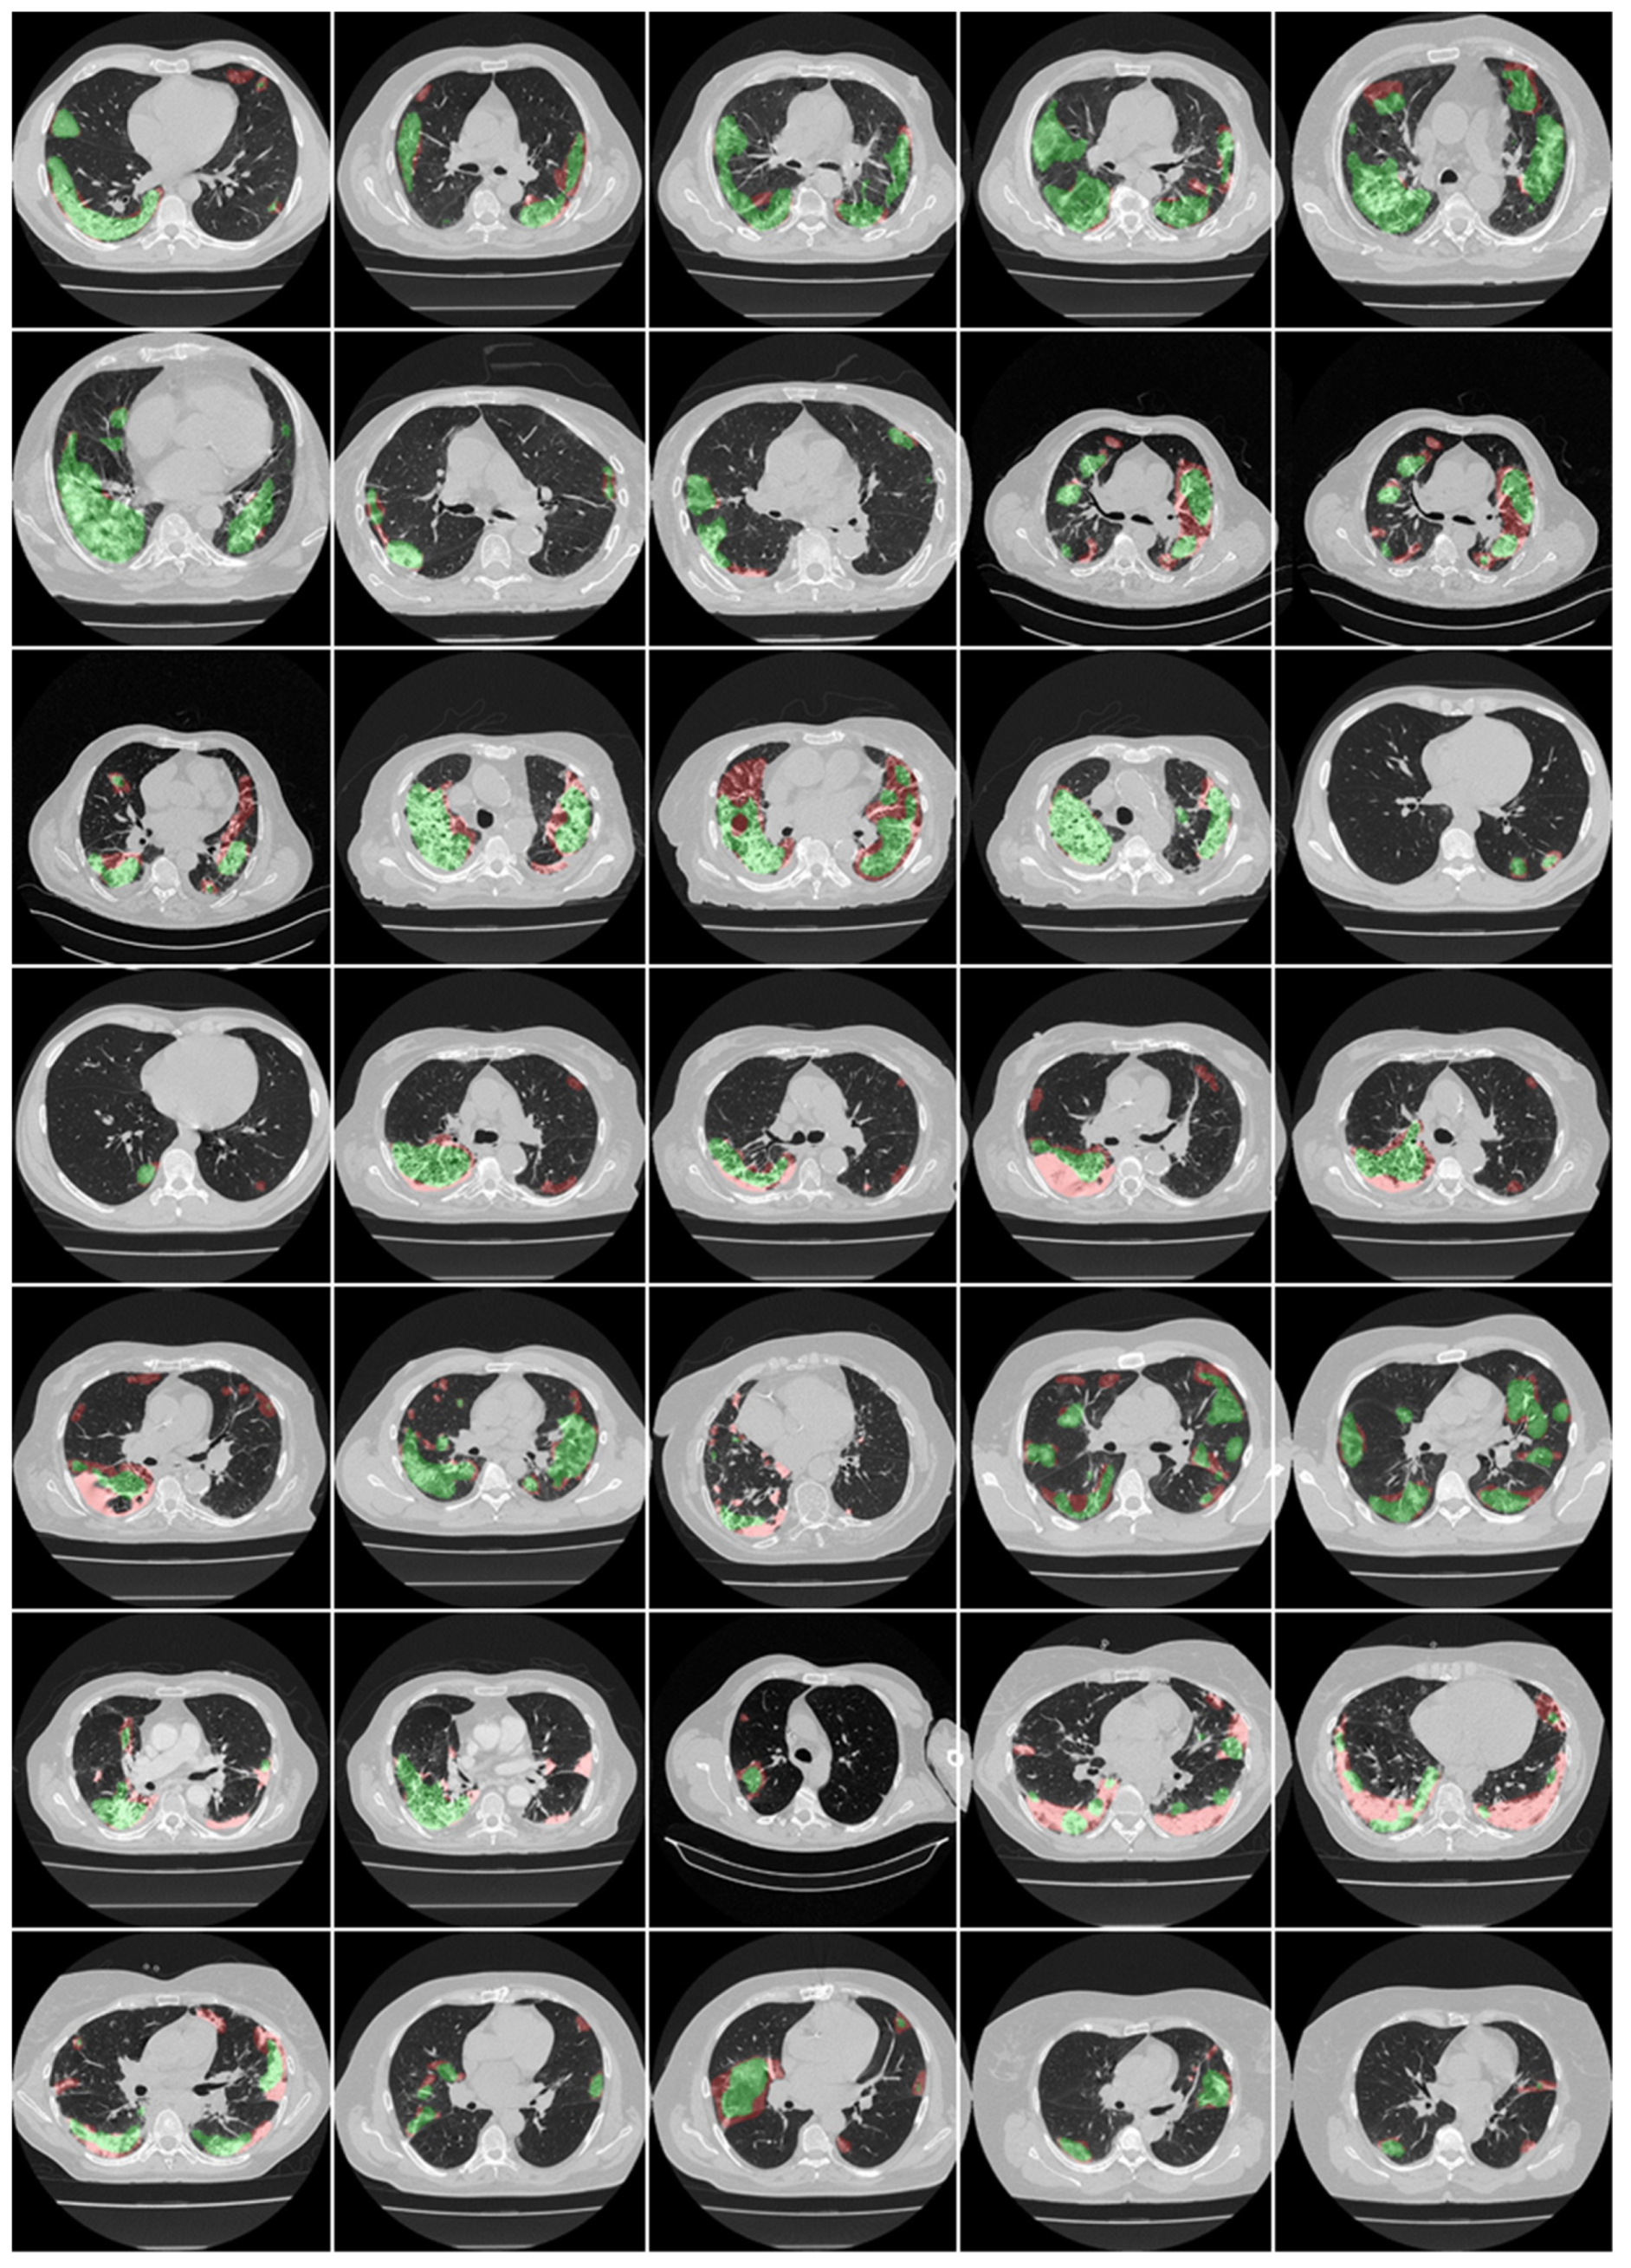

3.1. Results

3.2. Performance Evaluation